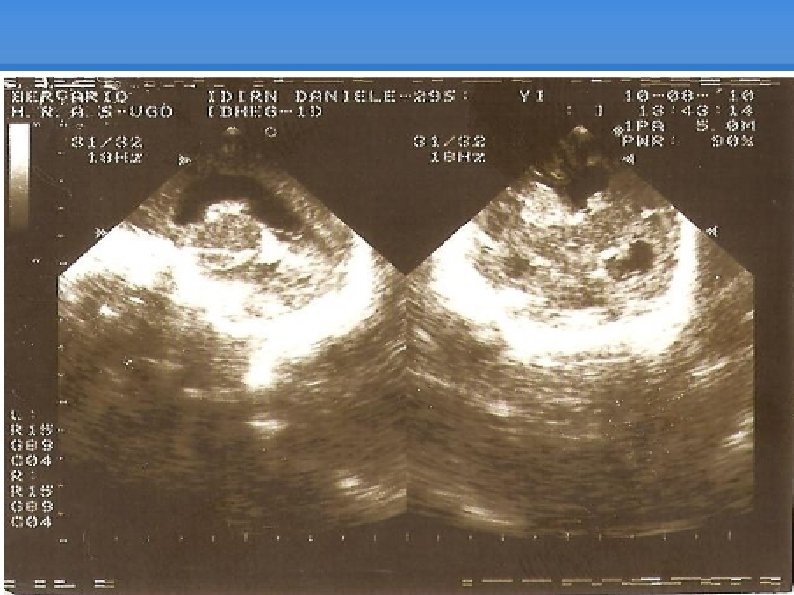

Só para ilustrar

Evolução UTIN (10: 35) : Eco transfontanelar mostrou infarto hemorrágico periventricular a direita (14: 00): Diurese em fralda com hematúria Aguardando concentrado de plaquetas; Gasometria: p. H=6, 67, p. O 2=7, 8, p. CO 2=96, 2, HCO 3=4, 9, BE=-23, Sat. O 2=6, 1 (16: 00): FC=50 bpm, feito reanimação, com FC subindo para 90 bpm; (17: 00): PCR irreversível;